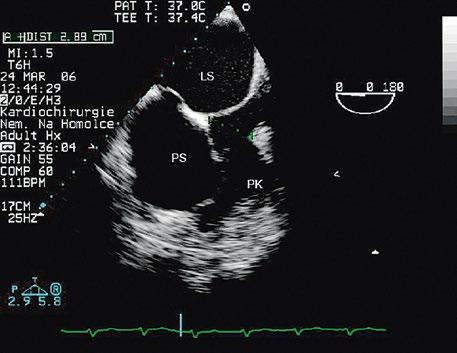

Obr. 45.36 Valvární pulmonální stenóza, doming cípů, jemné cípy, srůst komisur (TEE, longitudinální projekce) AP – kmen plicnice, PK – pravá komora, PS – pravá síň

valvuloplastika, a to bez ohledu na symptomy, při gradientu nad 64 mmHg; u symptomatických pacientů i při nižším gradientu.